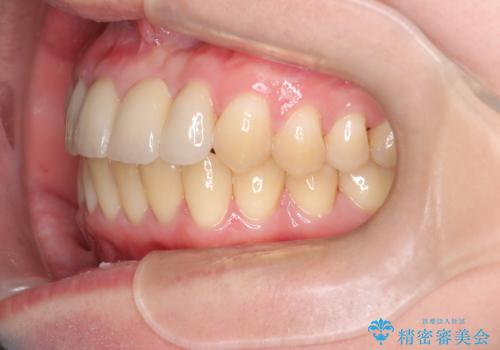

前歯の開咬とシザーズバイトを改善|インビザライン矯正

- 治療計画

前歯が噛まないため咀嚼が困難で、シザーズバイトにより噛み合わせに不調を感じていました。インビザラインを用いて、透明なマウスピースによる目立ちにくい矯正治療を実施。奥歯のシザーズバイトを改善した後、前歯の歯列を緻密に調整し、噛み合わせを整えました。定期的なマウスピース交換を通じて徐々に歯列が改善され、治療終了後には前歯が正常に咬合するようになり、噛み合わせの機能性と審美性が共に向上しました。